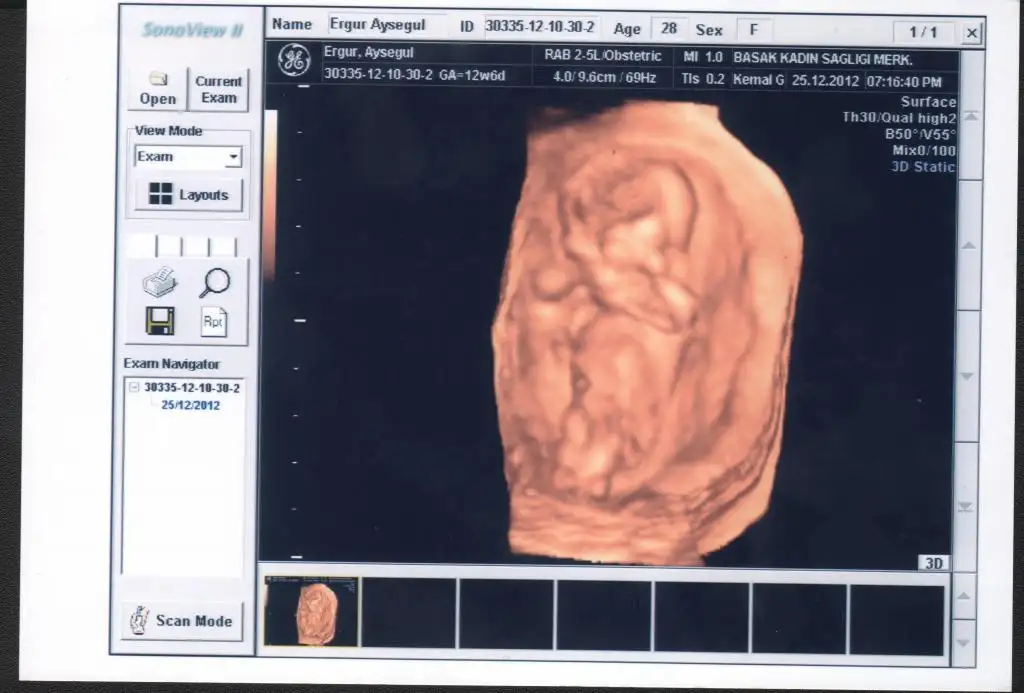

Eki Görüntüle 588130 Eki Görüntüle 588131

günaydın teyzelerimiz biz geldik

köftemiz iyi maşallah 6,6 cnm baştan popoya

karnı sırtı her bir yeri kapanmış hamd olsun organları oluşmuş

ense kalınlığımızda iyi çıktı

ikili taramanın usg bölümü gayet iyi dedi hocamız

yarın kan verecem oda temiz çıkarsa deymeyin keyfimize

teyzelerim maşşah diyin bana dio kuzu bayanlar duyulurulur

cinsiyeti sölemedi bu arada